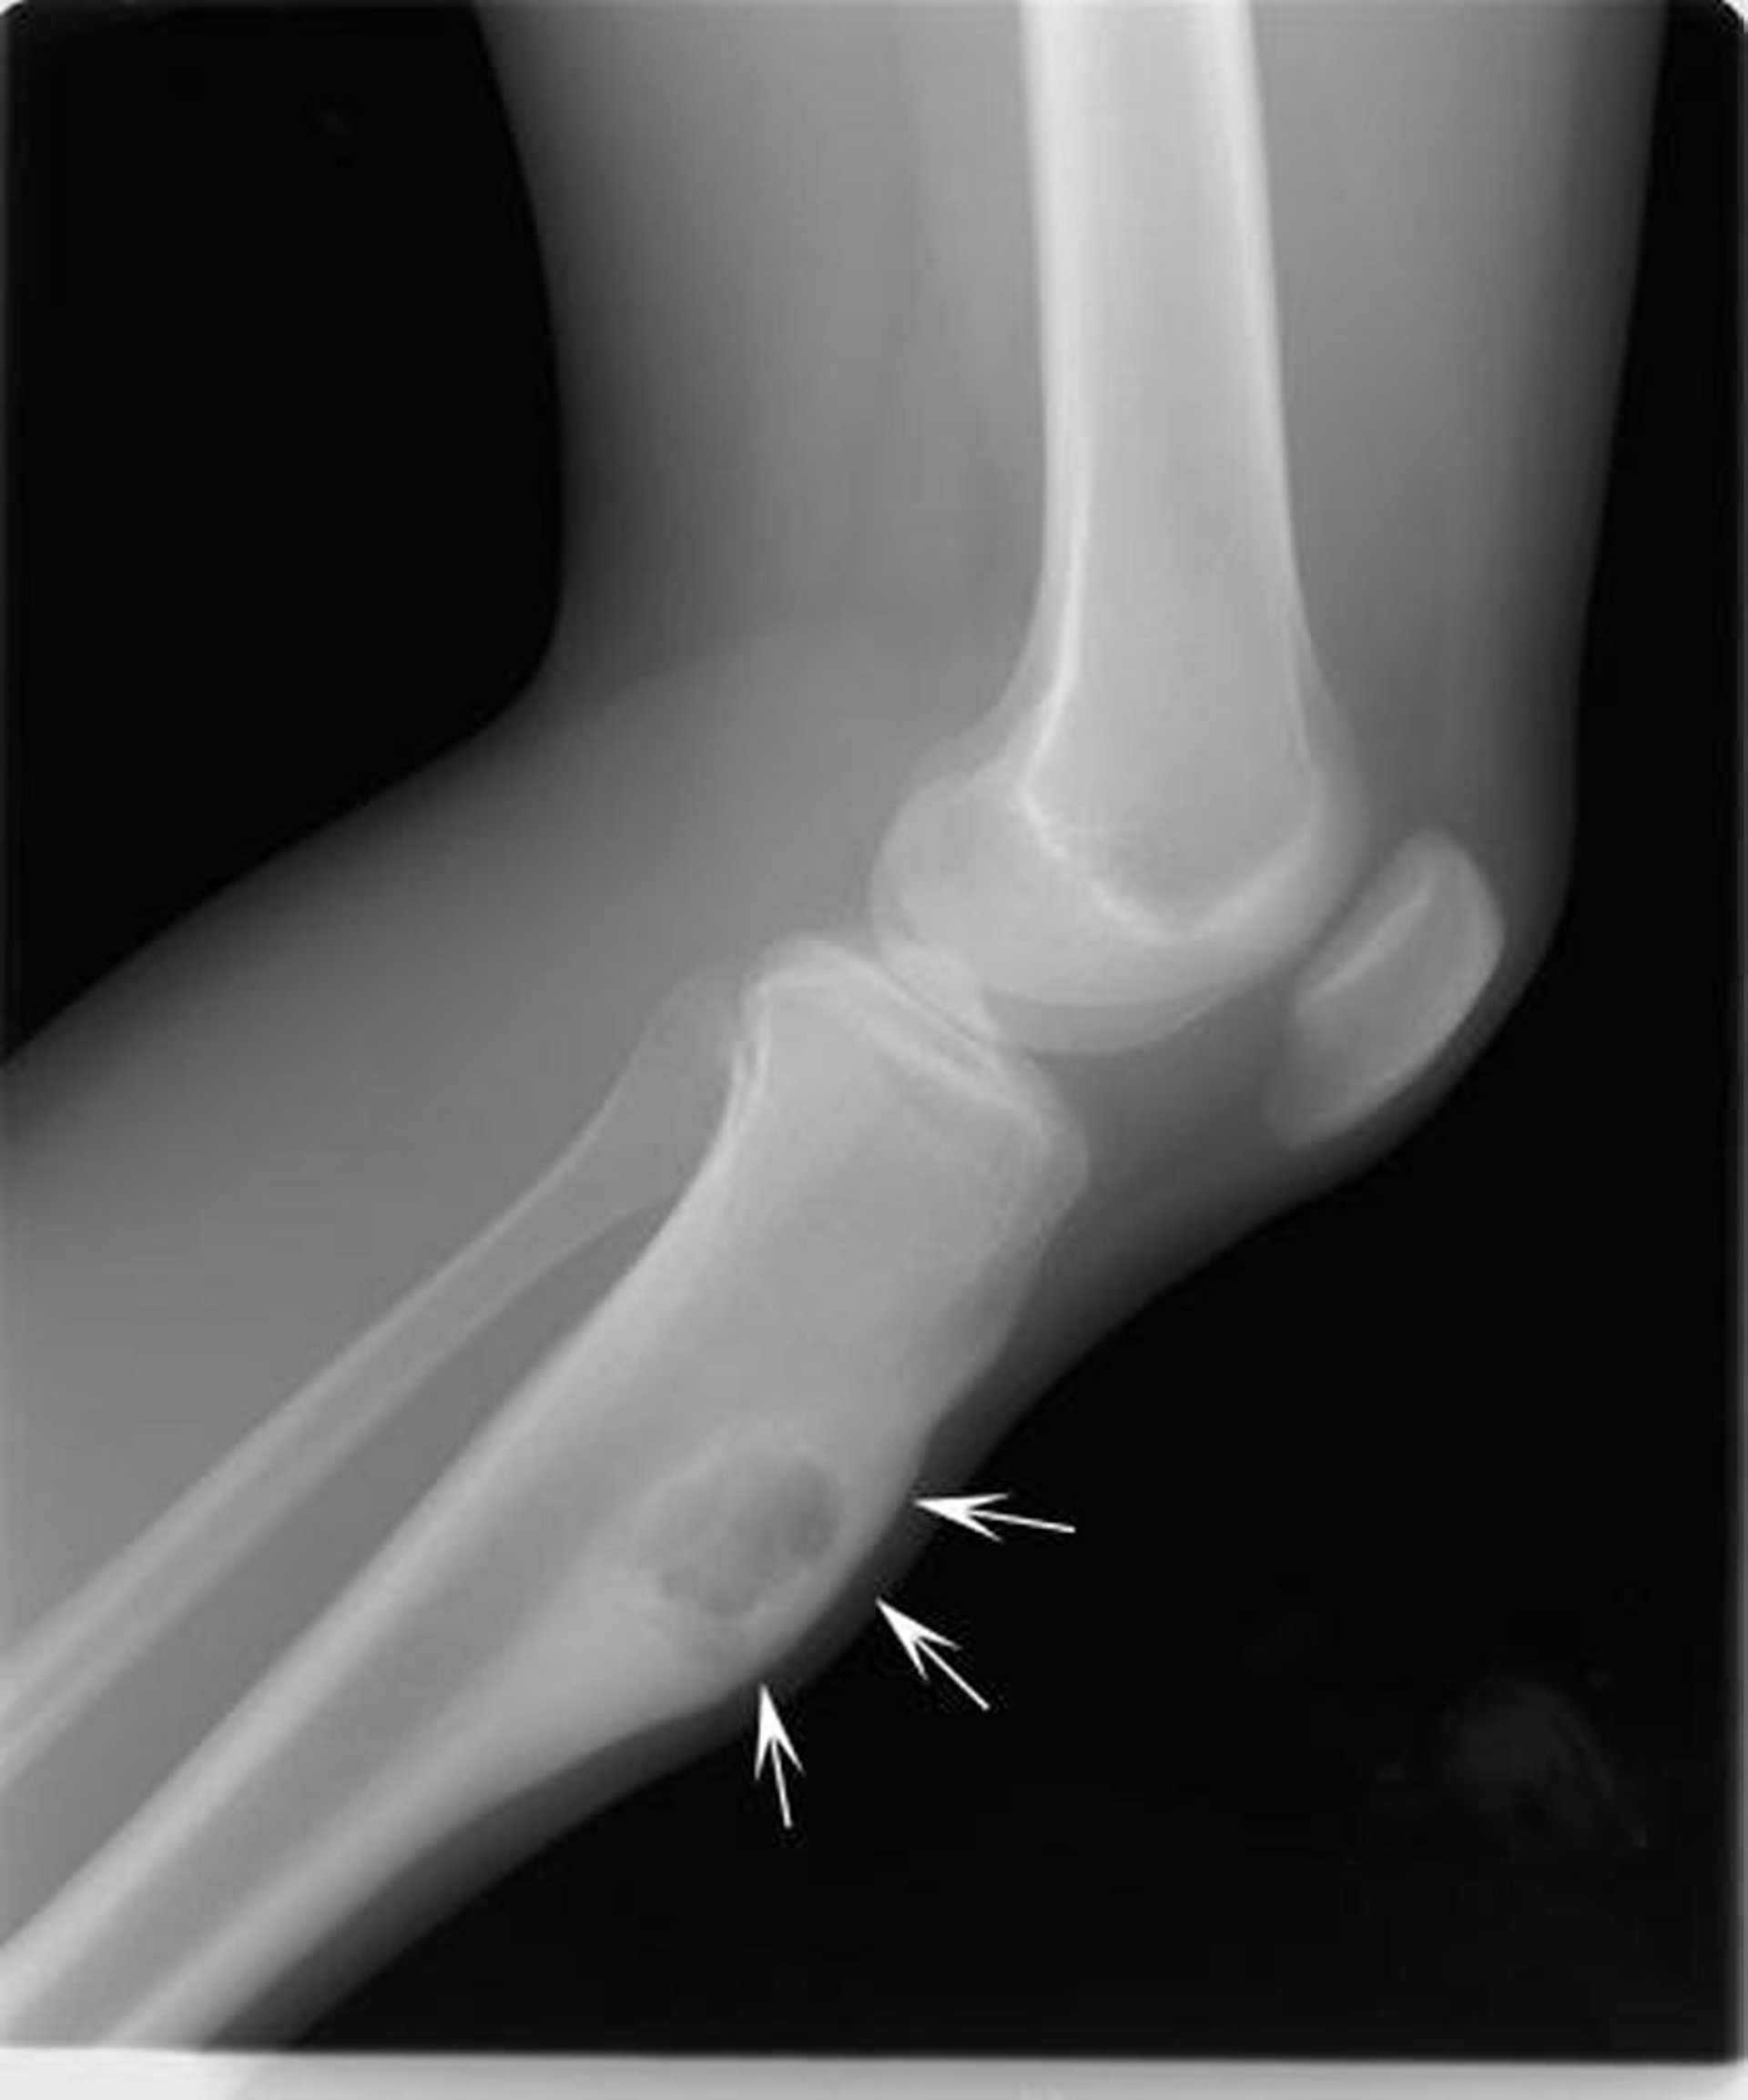

Radiografia del ginocchio che mostra un osteocondroma, la neoplasia sulla superficie del femore (frecce) al di sopra dell’articolazione del ginocchio.

Per gentile concessione di Michael J. Joyce, MD e Hakan Ilaslan, MD.

Generalmente, se cresce molto o se causa nuovi sintomi, l’osteocondroma viene rimosso chirurgicamente. Se, ad esempio, interferisce nella crescita ossea, causa dolore o preme su nervi, muscoli, vasi sanguigni o strutture circostanti, il tumore va rimosso.